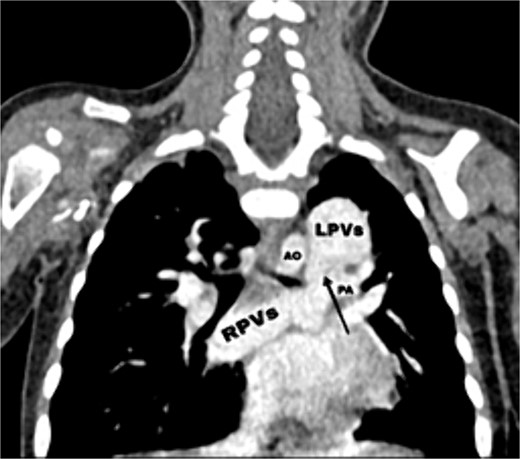

Transthoracic echocardiography (TTE) revealed an isolated supracardiac type of TAPVC, accompanied by a large ostium secundum atrial septal defect (ASD) measuring 9 mm, exhibiting a right-to-left shunt. Furthermore, there was evidence of dilatation in the right heart cavities and severe pulmonary hypertension (PHT = 65 mmHg). The common pulmonary confluence, measuring 12 mm in diameter, drained into the left innominate vein via a vertical vein. Confirmatory computed tomographic angiography (CTA) supported the diagnosis of supracardiac type TAPVC and identified stenosis along the venous pathway between the right and left pulmonary veins (Figs 1 and 2).

Axial (right) and coronal (left) postcontrast computed tomography sections: SVC: superior vena cava, VV: vertical vein, RA: right atrium, LA: left atrium, AO: aorta, PA: pulmonary artery, red star: The confluence of PVs.

CT scan showing the right pulmonary veins (RPVs) and left pulmonary veins (LPVs) join all together posterior to the left atrium (LA) and pulmonary artery (PA), also showing the stenosis within the venous confluence between the drain of the right pulmonary veins and the drain of the left pulmonary veins.